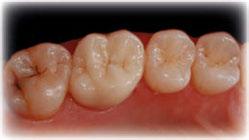

E-max CAD sobre implante

E-max CAD sobre diente natural

E-max CAD técnica “Cut-back”

E-max CAD “Monolítico”

E-max CAD “Monolítico” Pre

El innovador Disilicato de Litio (LS2) del sistema de cerámica vítrea IPS e.max CAD no solo ofece una altísima estética sino que también es de 2,5 a 3 veces más resistente 360 MPa que el resto de cerámicas de vidrio. Por ello, este material cubre todos los requerimientos estéticos y también representa una alternativa eficiente a las restauraciones unitarias de Zr02 (Zirconio).

El innovador Disilicato de Litio (LS2) del sistema de cerámica vítrea IPS e.max CAD no solo ofrece una altísima estética sino que también es de 2,5 a 3 veces más resistente 360 MPa que el resto de cerámicas de vidrio. Por ello, este material cubre todos los requerimientos estéticos y también representa una alternativa eficiente a las restauraciones unitarias de ZrO2. (Zirconio)

IPS e.max está avalado por la experiencia clínica que ha demostrado durante años, tanto en estética como en resistencia. La amplitud de elección del material, según el caso, en conjunción con la técnica empleada en nuestro laboratorio dotarán a los trabajos de la mayor estética para sus pacientes.